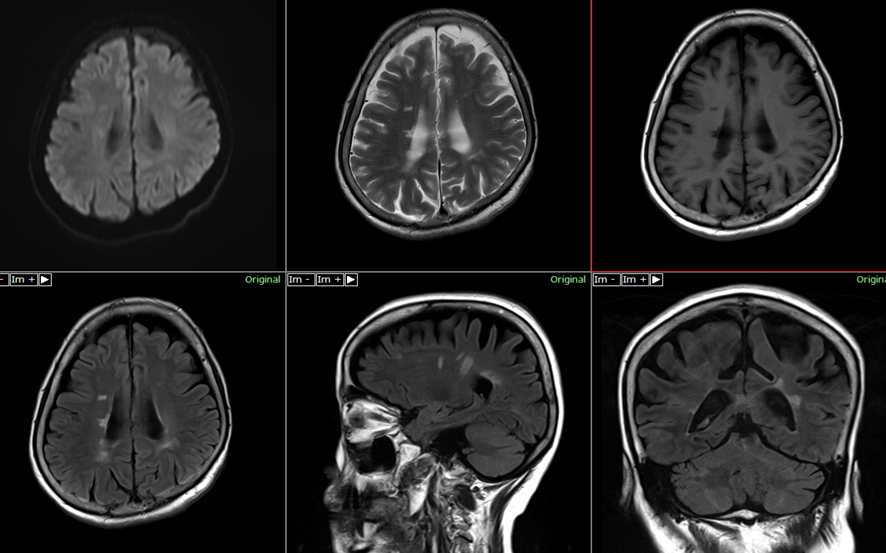

MS は、神経線維を取り囲んで保護する脂肪の鞘であるミエリンに損傷を与えることにより、中枢神経系に影響を与えます。その結果、神経線維自体が変化します。 MS の影響を受けた特定の神経線維は、感覚異常を含むさまざまなMS 症状を引き起こします。